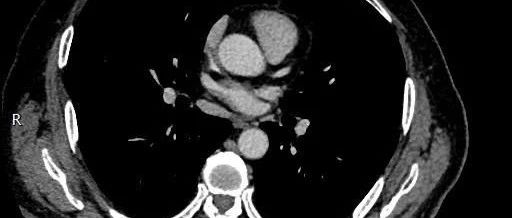

【临床病例(理)讨论】胸痛伴双肺多发磨玻璃影

2021年12月29日 星期三作者:李小钦  姚秀娟  陈正伟  李解珍  肖桂卿  陈愉生  谢宝松单位:福建省立医院呼吸与危重症医学科 福建医科大学省立临床医学院引用本文: 李小钦, 姚秀娟, 陈正伟, 等.  胸痛伴双肺多发磨玻璃影 [J] . 中华结核和呼吸杂志, 2021, 44(12) : 1131-1134. DOI: 10.3760/cma.j.cn1112147-20210325-00196....